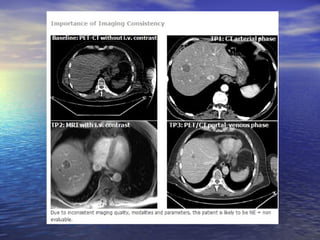

Diferença da avaliação em relação à fase do contraste

fase arterial                           Fase portal